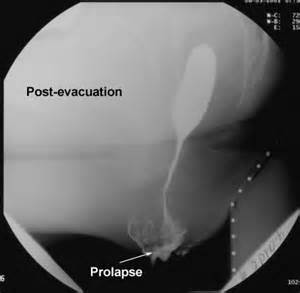

Hansı xəstəlikdə barium imaləsində görünüş “qurğuşun borunu” xatırladır?

Xroniki xoralı kolitdə

Xoralı kolitlərdə dərman verilməsinin özünəməxsus üsulu hansıdır?

İmalələr (steroid, 5-ASA)